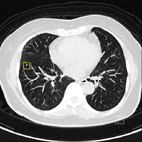

肺部篩檢使用的低劑量肺部電腦斷層掃描影像和常規性診斷用電腦斷層掃描的一致性。

肺部電腦斷層掃描使用CAD功能所偵測到的影像(左圖)。